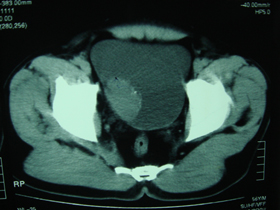

典型病例,男,56岁。无痛性血尿3月。

膀胱占位性病变,呈菜花状生长,考虑膀胱癌。 期待病理。